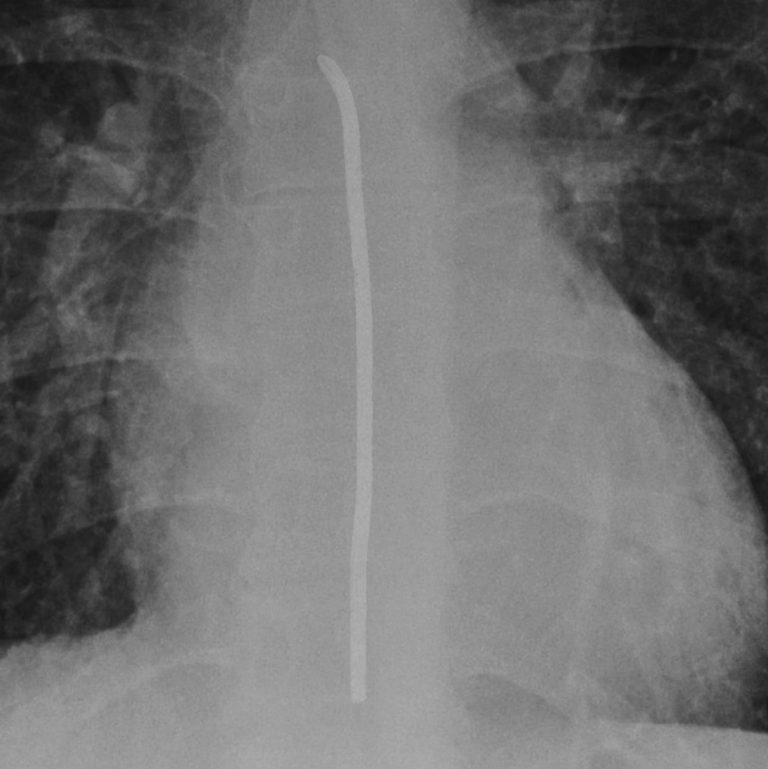

Nasogastric (NG) tube placement

Nasogastric tube position is a critical check. A tube that inadvertently tracks into the trachea and down a bronchus is dangerous: feeding through it can be fatal. To confirm safe placement on a chest X‑ray, I look for four features:

The tube must bisect the carina in the midline. If it bisects the carina, it is almost certainly within the oesophagus rather than the airway.

Next, does the tube pass the diaphragm in a central position?

Does the tube pass below the left hemidiaphragm? This is expected if is heading to the stomach and the stomach has a normal position.

Can you see the tube tip?

If you can satisfy all four conditions then you can say your NG tube is in the right place and is ready to use.

In patients with altered anatomy for example from a hiatus hernia or prior gastric surgery, the tube may take an unusual course. In such cases, compare with prior films or if really necessary you can perform a film post contrast, fluoroscopy or a CT scan for reassurance.

The four rules of nasogastric (NG) tube placement on X-Ray